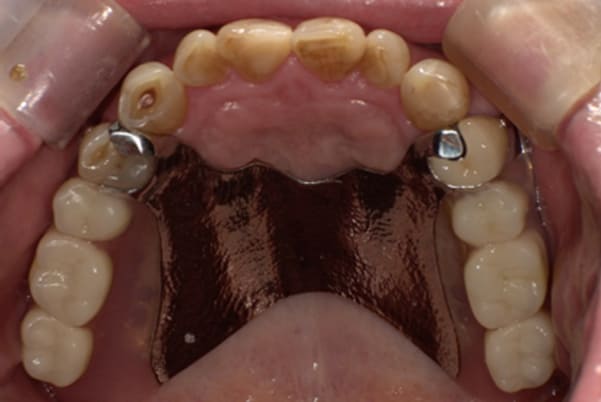

症例レポート[CASE.02]

入れ歯がカパカパして痛い、

歯がぐらぐらする

- 男性(60代)

- 入れ歯がカパカパする、歯がぐらぐらして痛い、食いしばれない

- 上顎精密総金属床総入れ歯

- 下顎精密金属床部分入れ歯

上の前歯が重度歯周病により動揺し、残せない状態のため、入れ歯も動揺がありました。

ご自身の歯に負担の少ないバネ、また見た目も改善

バネをかける歯は繋げることで強度を増し、歯への負担を軽減し、歯の寿命を長くする設計へ。

バネがかかる歯の被せ物は、歯への負担を減らし、入れ歯が動きにくいようになる形態をあらかじめ付与することで、より入れ歯の機能が高まります。

治療を行う際、被せ物や入れ歯は、別々に考えるのではなく、一口腔単位としてお口全体のことを考え最良の治療計画を立てることが歯の寿命、機能効果を向上させるため、専門医としてこのことは常に心掛けて治療を行っています。

残りの歯に負担がかからないよう、被せ物と入れ歯の一体化を図った入れ歯

治療前は上下奥歯の入れ歯が削れていることで、かみ合わせが低くなり唇もつむった状態でした。

かみ合わせを適切な高さに戻したことで、本来の自然な口元へ。